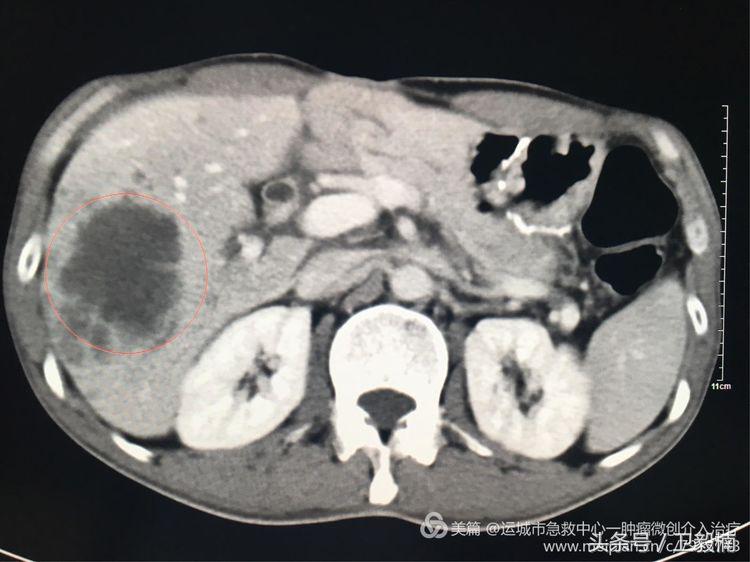

2017年6月患者因腹痛,饮食差来我院复查行腹部增强CT:提示肝内多发转移。

上腹部增强CT